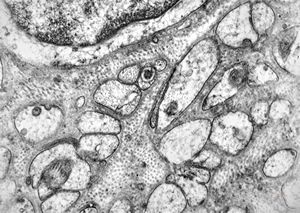

M, 17y. | Fabry disease

M, 48y. | Fabry disease